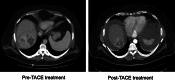

Results: Hepatitis B vaccination and treatment of chronic hepatitis B and C are important measures for HCC prevention. Screening and surveillance for HCC using ultrasonogram and alpha-fetoprotein estimation are directed toward cirrhotics and hepatitis B patients at high risk of HCC. If detected at an early stage, curative treatments for HCC can be used such as tumor resection, ablation and liver transplantation. HCC patients without curative options are managed by loco-regional therapies and systemic chemotherapy. Loco-regional treatments include trans-arterial chemoembolization, radioembolization and combinations of loco-regional plus systemic therapies. Currently, sorafenib is the only FDA-approved systemic therapy and newer better chemotherapeutic agents are being investigated. Palliative care for terminally ill patients with metastatic disease and/or poor functional status focusses on comfort care and symptom control.